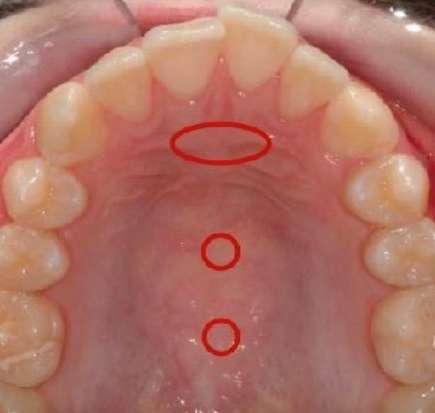

Clasificación de frenillos

La clasificación de frenillos es variada. Para determinar si intervenir un frenillo o no, lo correcto es evaluar la forma, la apariencia y la función para poder determinar junto al equipo transdisciplinario (logopeda, puericultora, odontopediatra, ortodoncista, otorrino, fisioterapeuta, etc.) el camino a seguir. Existen varias formas de evaluación, entre ellas Coryllos, Kotlow, Martinelli, Haselbaker, etc. Como elección personal de preferencia: Haselbaker ya que evalúa la apariencia y la función, así como Frelac Barcelona y las clasificaciones en base al rango de movilidad anterior y posterior del Dr. Zaghi, además de realizar una anamnesis completa de nuestro paciente. Existen diferentes tipos de frenillos: anterior, mixto, posterior y submucoso (tipo 1, 2, 3 y 4). Los más perjudiciales para la lactancia materna son el posterior y el mucoso que no permiten realizar una correcta peristalsis durante el amamantamiento con sus consecuencias sobre el binomio madre-lactante (Imagen 3).